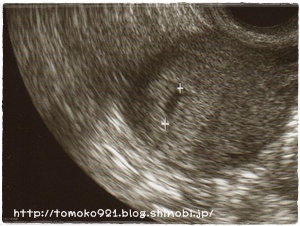

8月18日に、病院に行ってみると・・・胎嚢を確認!

090818.jpg

しかし、この時点では赤ちゃんは見えず。

このエコー写真を撮った丸2週間後の9月1日にもう一度病院へ行きました。

090901.jpg

赤ちゃん発見!!

袋の上の方にいてはりました(*´∀`*)

心臓も動いているのが分かりました~!!